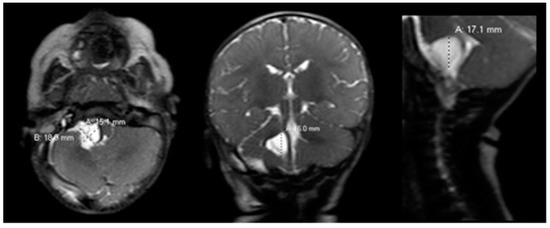

Postoperatively, the patient returned to the pediatric intensive care unit and was extubated. Postoperative rapid-sequence MRI showed a well-decompressed cyst with decreased mass effect on the pons, medulla and cerebellum (Figure 2).

Figure 2.

Postoperative brain MRI scan. The postoperative brain MRI scan on postoperative day 1 (left = axial; middle = coronal; right = sagittal) T2 sequences showed interval decompression of the prior known arachnoid cyst with decreased mass effect. MRI = magnetic resonance imaging.